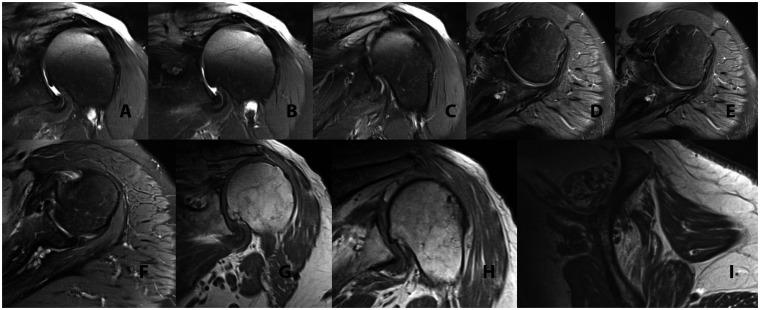

Reverse shoulder arthroplasty is a useful procedure with broadening applications, but it has the best outcomes when used for rotator cuff tear arthropathy. However, this procedure is not without complications. While scapular notching and aseptic loosening are more common complications that have been extensively studied in the literature, dissociation of the glenoid component and incomplete glenosphere seating has not received much attention. Specifically, little research has explored appropriate management of incomplete seating of the glenosphere component, and no gold standard for treatment of this complication has emerged. In the case described here, an elderly patient with an incompletely seated glenosphere component post-operatively opted to pursue conservative management in order to avoid revision surgery if possible. The partially engaged, superiorly directed components in this case exhibited spontaneous complete and symmetric seating of the glenosphere between six and twelve months post-operatively, indicating that conservative management of this complication in low-demand patients may be a viable option to avoid the risks associated with revision surgery. Further research should be pursued to explore what patient and prosthesis design factors may be suited to observation with serial radiographs when incomplete seating of the glenosphere component occurs.

反肩关节置换术是一种应用日益广泛的有效手术,但用于肩袖撕裂性关节病时效果最佳。然而,该手术并非没有并发症。虽然肩胛切迹和无菌性松动是文献中已广泛研究的较常见并发症,但关节盂组件分离和关节盂球窝不完全就位并未受到太多关注。具体而言,很少有研究探讨关节盂球窝组件不完全就位的适当处理方法,且尚未出现治疗该并发症的金标准。在此所述病例中,一名老年患者术后关节盂球窝组件就位不完全,为尽可能避免翻修手术,选择采取保守治疗。该病例中部分嵌入、向上指向的组件在术后6至12个月内关节盂球窝自发完全且对称就位,表明对需求较低的患者的这种并发症采取保守治疗可能是避免翻修手术相关风险的可行选择。应进一步开展研究,以探索当关节盂球窝组件不完全就位时,哪些患者和假体设计因素可能适合通过系列X线片进行观察。